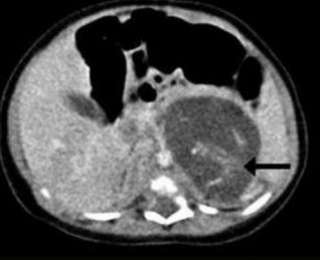

Когда только начались проблемы со здоровьем новорожденной, ее передали доктору Ю Кай-ману, акушеру-гинекологу, работающему в Больнице Королевы Елизаветы в Гонконге, заподозрив наличие опухоли у младенца. Перинатальный ультразвук обнаружил в теле ребенка необычную массу, но врачи не могли понять, что это. Когда девочке было всего 3 недели, была проведена операция, и хирурги обнаружили два плода, находившихся между ее печенью и почками.

Один плод весил 9,3 грамма, другой — 14,2 грамма, что соответствовало примерно 8–10 неделям беременности. Каждый эмбрион был присоединен к плаценте девочки пуповиной.